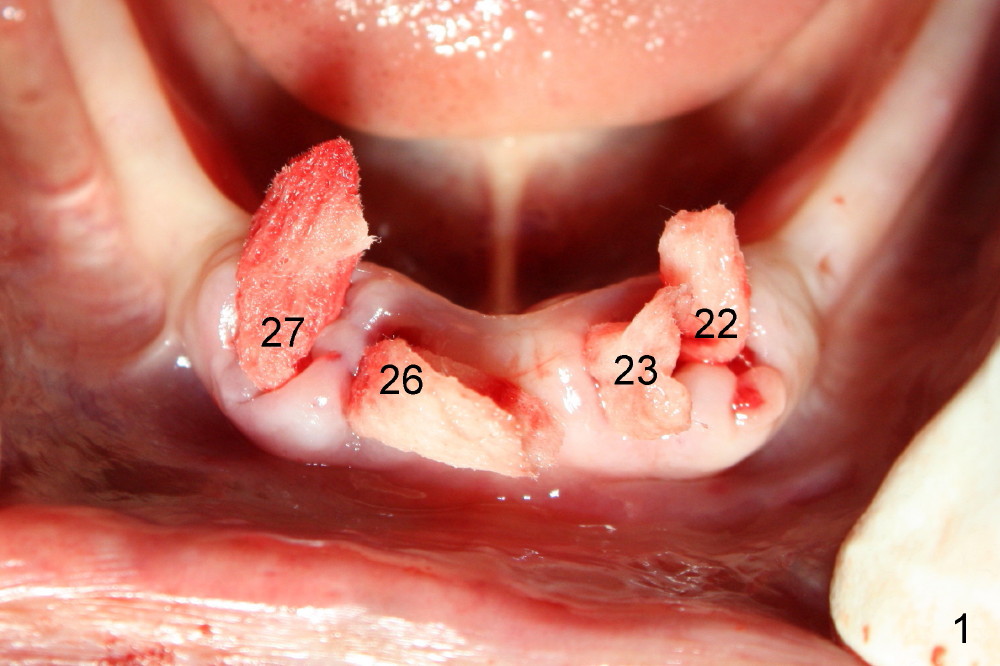

These difficulties are related to limited socket exposure during osteotomy. The threads of the implants (<) are exposed as early as one week postop (Fig.6) and last 4 months postop (Fig.7). Immediate difficulty is that a lot of acrylic has to be removed to accommodate the balls. In one word, restorative space is not wide enough. Raising flaps with alveoloplasty prior to osteotomy could solve the problems (Fig.4,5).